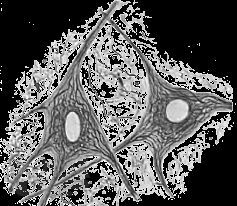

Диагностика микропрепаратов

Мустафина Л. Р. Диагностика микропрепаратов : Учебное пособие по общему и частному курсу гистологии для самоподготовки студентов лечебного и педиатрического факультетов / Л. Р. Мустафина, С. В. Логвинов, Е. Ю. Варакута. - Томск : Издательство СибГМУ, 2018. - 46 c. - Текст : электронный // ЭБС "Букап" : [сайт]. - URL : https://www.books-up.ru/ru/book/diagnostika-mikropreparatov-9283102/ (дата обращения: 16.02.2026). - Режим доступа : по подписке.

Учебное пособие предназначено для самостоятельной работы с микропрепаратами при подготовке к итоговым практическим занятиям по общему и частному курсу гистологии студентов I и II курсов лечебного и педиатрического факультетов.